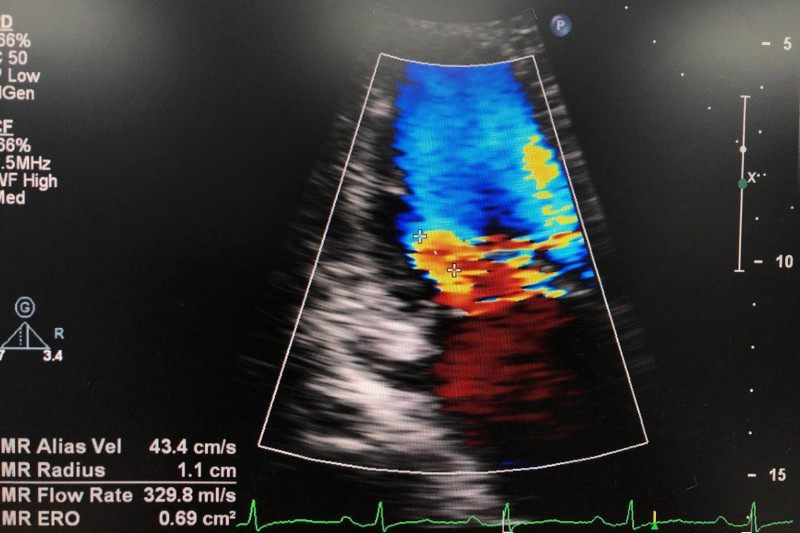

Một số hình ảnh hở van tim 2 lá 1/4: